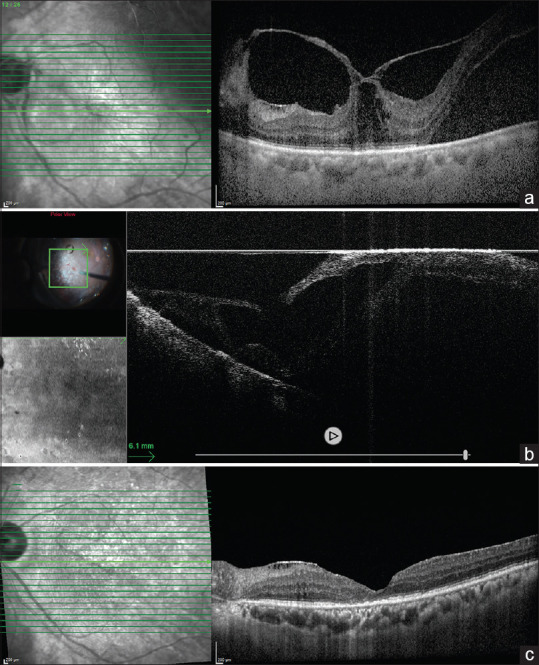

Intraoperative optical coherence tomography (iOCT) has been applied and studied in a variety of vitreoretinal surgeries for its feasibility, safety, and outcomes for years. Common scenarios include membrane peeling procedures, retinal detachments, choroidal-retinal biopsies, Argus implants, and subretinal injections. iOCT offers the surgeon a better understanding of the retinal microarchitectural changes and timely intraoperative feedback, directing a future view of precision surgery. However, this technology has not been widely adopted due to its limitations including cost, surgeons' habits, lack of compatible equipment, software limitations, and so on. We aim to highlight the importance of iOCT in guiding clinical-relevant surgical decisions by illustrating two vitreoretinal cases that are complex and less frequently encountered.